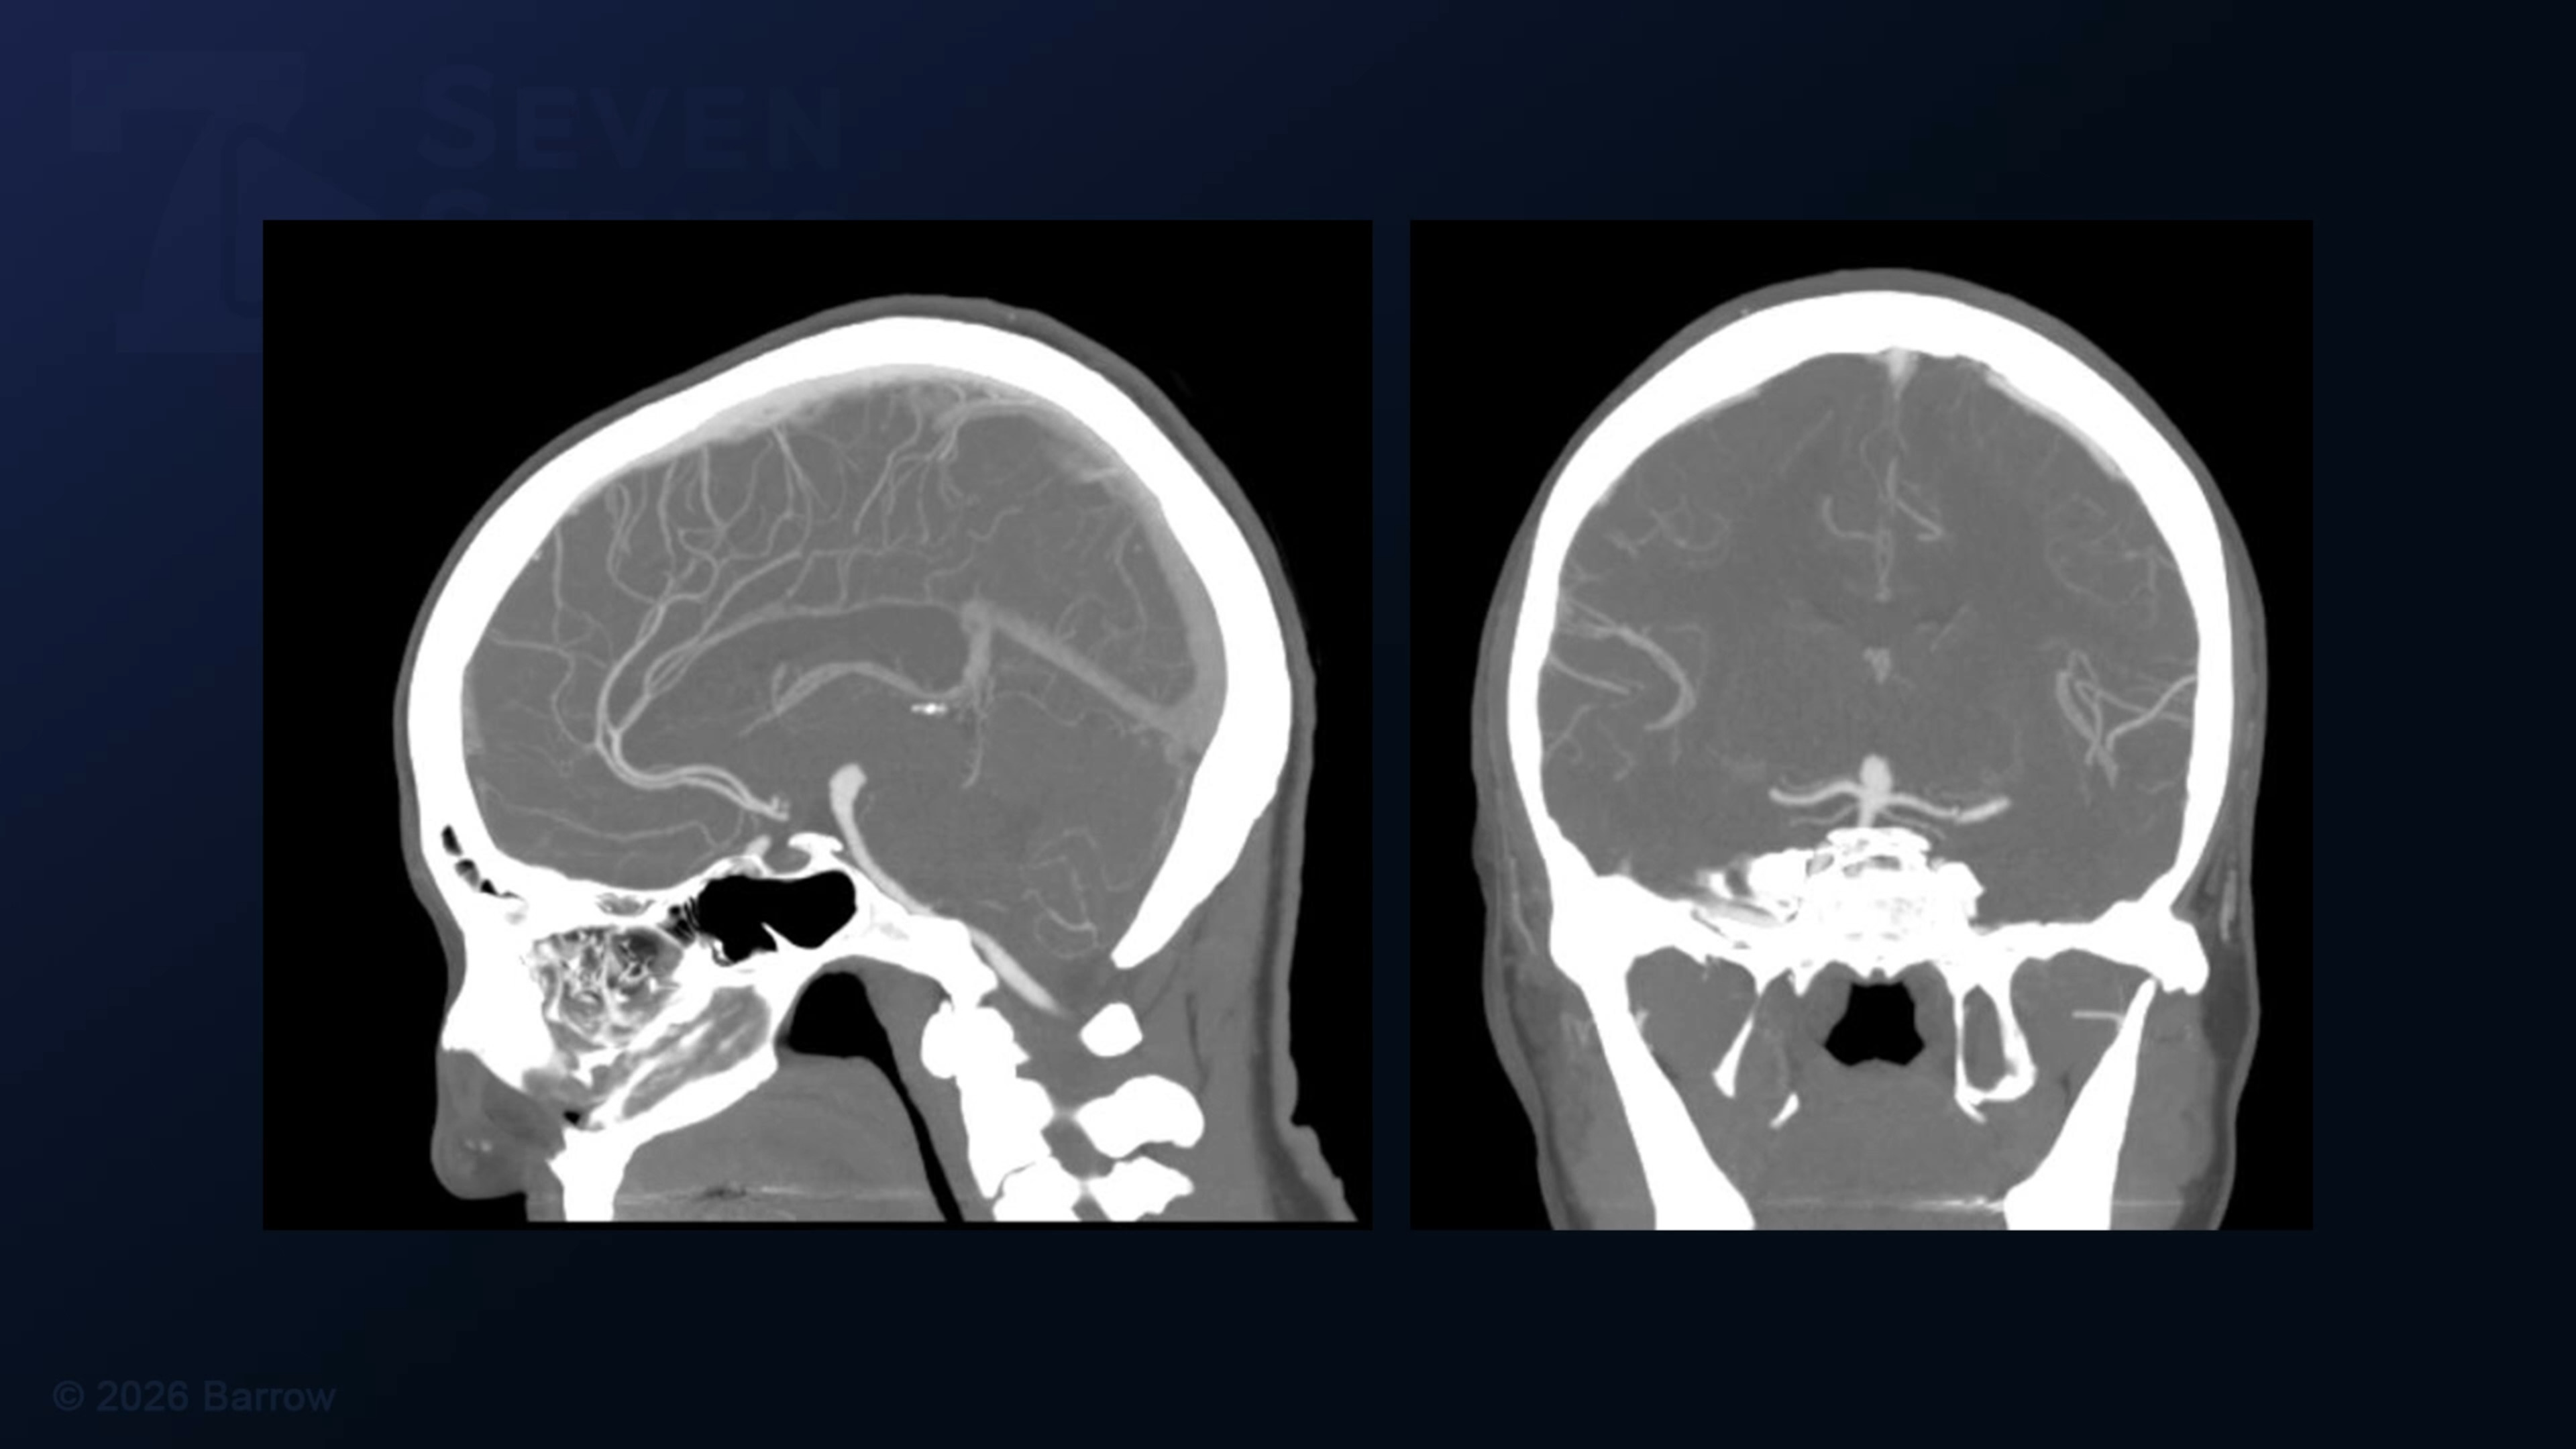

Episode 507 of Seven Series shows an orbitozygomatic pterional craniotomy for clipping of a basilar bifurcation aneurysm.